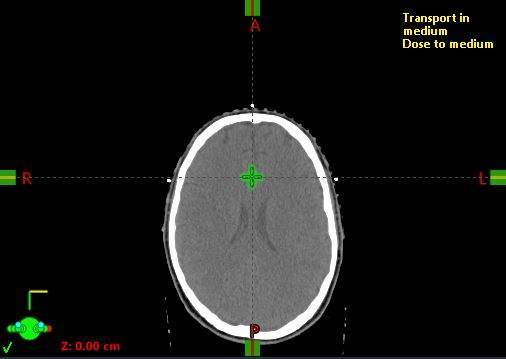

Once imported, the CT scan is used to localize the patient—a system of coordinates and markings is employed to track the patient’s geometric position in space.

At the time of simulation, BBs are often used to mark the setup location in a triangular fashion, typically with three points (anterior and lateral). We will set the user origin or localization at this location.

Next, we will set the user origin for the image, aligning the coordinate systems with the TPS.

To localize the patient, scroll to the slice containing the BBs and set the user origin at the viewing plane intersection.

To “localize” the patient, scroll to the slice where the BBs are visible and set the “User Origin” to the slice where the three markers intersect (viewing plane intersection).